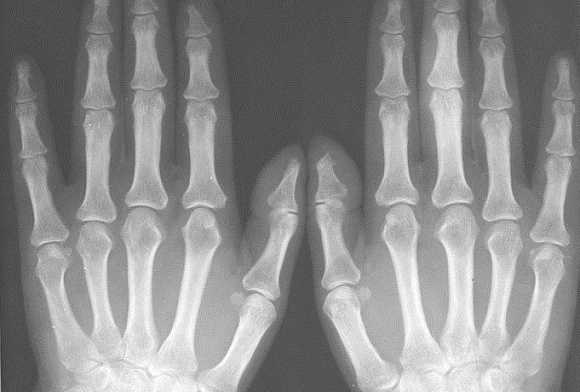

Ревматические поражения

Рентген кистей рук при ревматоидном артрите - важная диагностическая процедура, которая позволяет точно выявить стадию развития заболевания. Главными рентген-признаками данной патологии являются припухлости мягких тканей сустава. Также об артрите свидетельствует незначительное сужение межсуставной щели и визуализируемый остеопороз. На более поздних стадиях развития патологии будут видны эрозии костей, которые имеют вид некрупных краевых дефектов в суставных концах костей. В эпифизах костей фаланг пальцев могут виднеться округлые просветления.

При проведении рентгена кистей рук с функцией увеличения изображения можно выявить нарушение целостности замыкающих пластинок уже на первых стадиях развития ревматоидного артрита. По мере прогрессирования заболевания будет наблюдаться ухудшение картины - сустав будет становиться всё уже, появятся очаги эрозии, станет ярче выраженность остеопороза. В результате разрушения суставных концов кости могут появиться подвывихи.